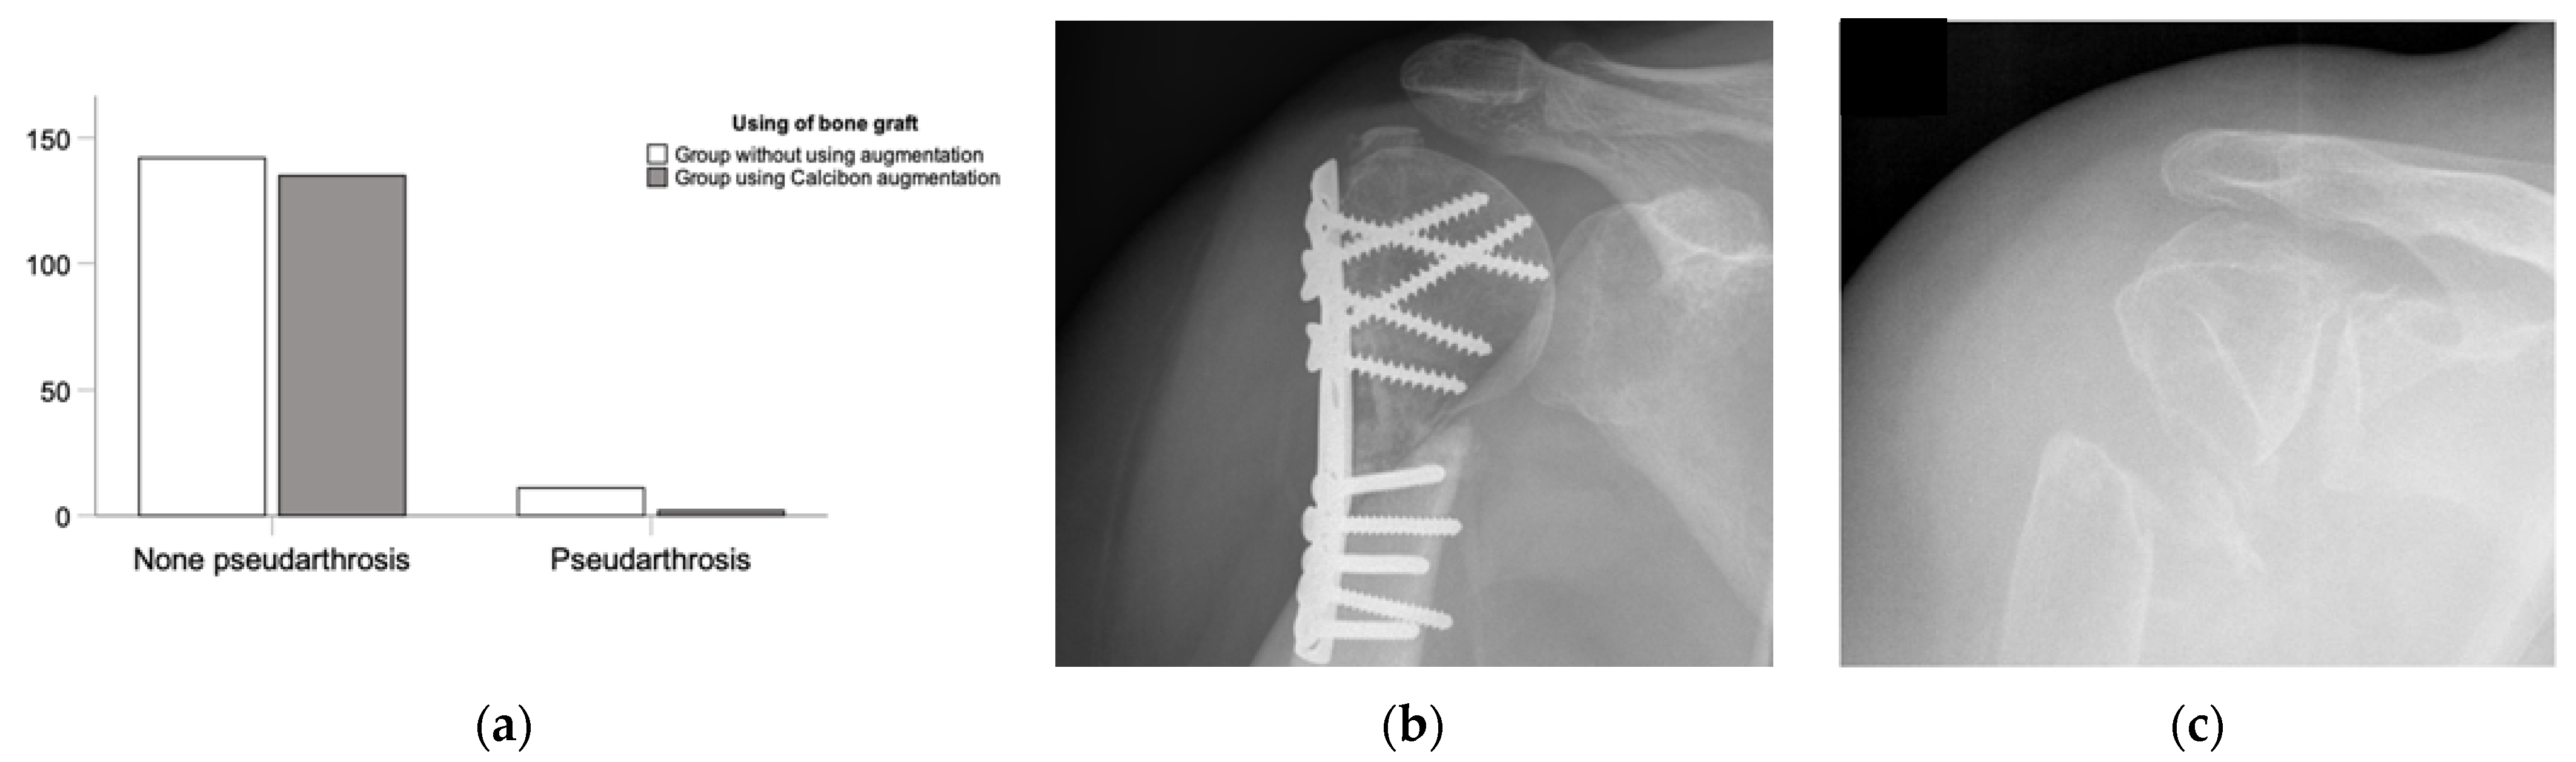

3.2. Clinical Outcome—Complications

In terms of clinical outcomes and complications, we observed various postoperative complexities, with a range and mean of (0:4; 0.5 ± 0.74) complications per patient. Specifically, fractures treated without an added bone graft showed significantly more postoperative complications (0:3; 0.64 ± 0.74) compared with the CP group (0:4; 0.34 ± 0.70) (p < 0.001). These complications included pseudarthrosis and other orthopedic issues. Notably, significant differences were observed in comparing (1) pseudarthrosis, (2) other complications, and (3) no complications between the CP augmentation and ED treatment groups. Overall, the use of the CP bone substitute showed an improvement in complications (p < 0.001). Significance was also evident between the ED and CP groups concerning pseudarthrosis and no pseudarthrosis (p = 0.022) (Figure 4). Additionally, there were fewer instances of post-traumatic arthrosis (p = 0.01) and neurological issues (p < 0.001) in the CP augmentation group, as indicated in the overview of complications (Figure 5).

Figure 4.

Overview of pseudarthrosis post-surgery. (a) Rate of pseudarthrosis in the ED group compared with the rate of pseudarthrosis in the NHA group with significant differences. (b) An example of the clinical examination of a recent fracture treatment. (c) Conventional radiograph of a pseudarthrosis 18 years post-trauma by X-ray.